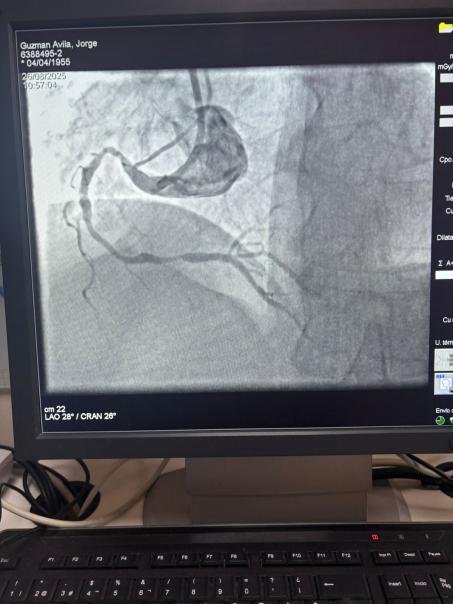

Wir sind stolz darauf, einen bemerkens werten Fall aus dem Krankenhaus Sótero del Río, Chile, zu teilen, in dem Dr. Martín Valde benito eine stark verkalckte Läsion in der rechten Koronar arterie (erste Kurve) mit unserem Vess crack Koronar-IVL-Ballon dilatation katheters ystem erfolgreich behandelte.

Das Verfahren erzielte hervorragende Ergebnisse, wobei die verkalckte Region effektiv geknackt und der Gefäß fluss wieder hergestellt wurde. Dies ist ein weiterer Meilenstein bei der Erweiterung des globalen Zugangs zu fortschritt lichen Lösungen für die komplexe Koronar verkalkung.

Der Vergleich zwischen den angio grafischen Bildern vor und nach dem Eingriff zeigt deutlich die signifikanten klinischen Auswirkungen unserer IVL-Technologie.